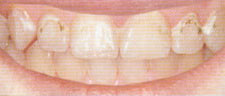

Кариес на гладких поверхностях: На открытых поверхностях определить кариес не трудно. Часто о наличии кариеса Сбидетельствуют «меловидные пятна», которые также нарушают эстетику зубов.

С помощью Icon можно без бормашины лечить даже такие формы кариеса, при этом зубы восстанавливают свой естественный цвет. Чаще всего кариозные пятна успешно удаляются в течение одной процедуры - за одно посещение.

Кариес и результаты лечения